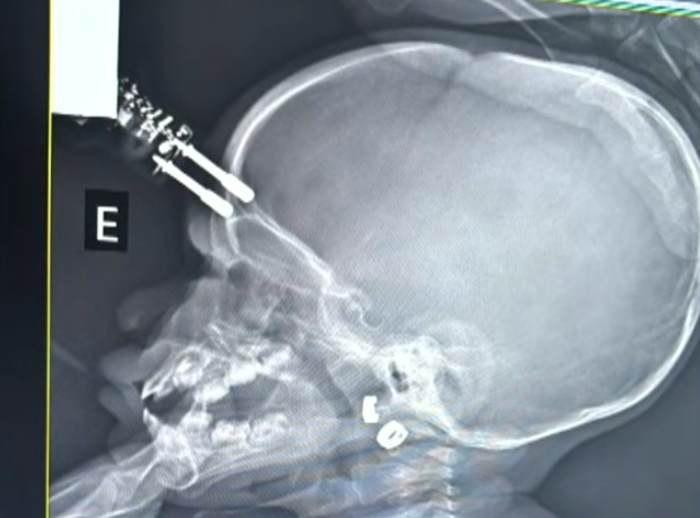

Criança fica com carregador cravado na testa ao cair da cama

Uma menina de 1 ano passou por uma cirurgia de urgência na terça-feira (13/1), após sofrer um acidente doméstico em Divinópolis, no Centro-Oeste de Minas Gerais. A criança caiu da cama e teve um carregador cravado na testa.

De acordo com informações médicas, o acidente ocorreu no momento em que a mãe da bebê foi ao banheiro. A criança estava com o carregador na mão quando caiu da cama, o que provocou a perfuração na cabeça.

A menina foi rapidamente encaminhada para atendimento médico e levada ao centro cirúrgico. No local, passou por procedimentos de limpeza, retirada do objeto, lavagem, fechamento e reconstrução da área atingida.

O neurocirurgião Bruno Castro, responsável pelo atendimento, informou que a criança segue em observação. Até o momento, não há sinais de sequelas neurológicas.

Foto: Reprodução/Bruno Castro